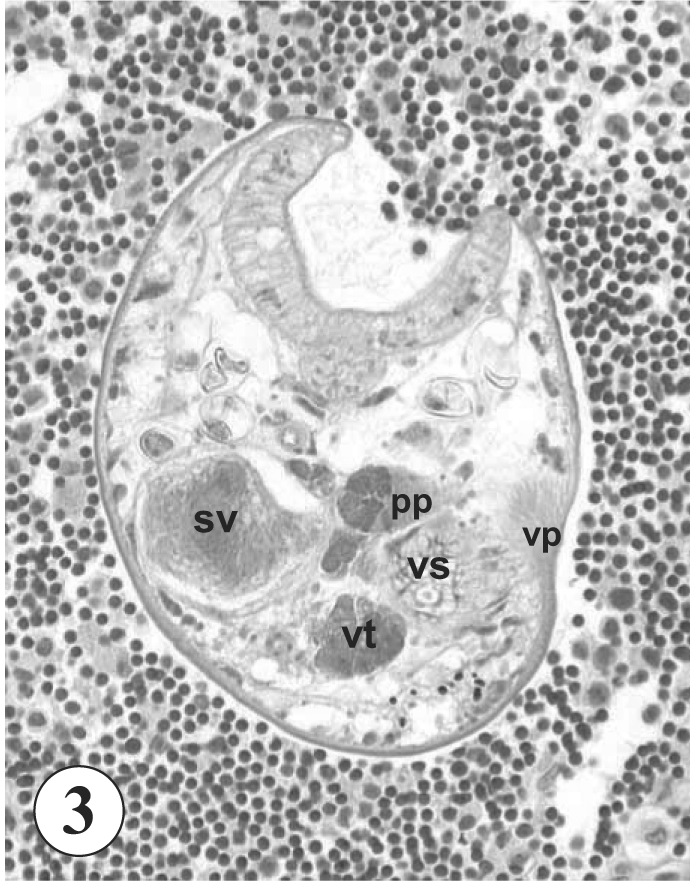

A 65-year old Korean man, living in Mokpo-city, Jeollanam-do, visited a local clinic with clinical complaints of right upper quadrant pain and indigestion in November, 2002. He also suffered from anorexia and dyspepsia. A fecal examination conducted at the time revealed no special parasite eggs or cysts. Colonoscopy and biopsy revealed the presence of a carcinoma of neuroendocrine origin at the ascending colon. He was transferred to Samsung Medical Center, where liver metastasis of the carcinoma was discovered. A palliative right hemicolectomy, small bowel resection, and anastomosis were performed, and the surgical pathology specimen revealed inflammatory reactions including villous atrophy and crypt hyperplasia of the excised colonic mucosa (

Fig. 1). Moreover, an adult fluke of

Fig. 1Section of the colon showing the mucosal layer. The mucosa shows villous atrophy and crypt hyperplasia, and no worm is observed in this area. H-E stain. x 40.